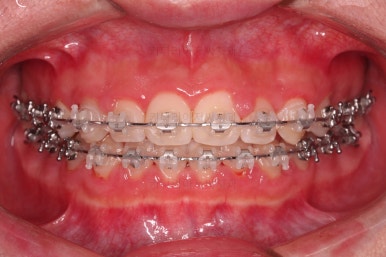

악궁확장 이 후 브라켓을 부착합니다.

이번 환자분이 선택하신 장치는 엠파워 클리어라고 하는 자가결찰 세라믹 장치인데요.

철사를 스스로(자가) 묶을 수(결찰) 있는 뚜껑이 달린 세라믹 성분의 장치입니다.

대표적인 장치가 클리피씨 장치이며 클리피는 일본회사, 동래교정치과 키다리아저씨치과가 쓰는 엠파워는 미국회사라는 차이가 있고 큰 틀에서는 동일한 계열의 장치입니다.